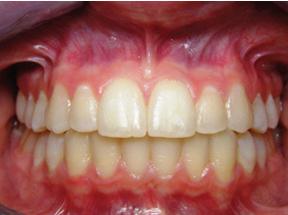

By Karl A. Smith, DDS, MS

Lasers have long been the standard of care in medicine for many surgical and cosmetic procedures. Lasers are used for vision correction, wrinkle and hair removal, vein therapy, and anti-aging treatments.

In the world of dental care, advancements like laser dentistry and laser periodontal therapy are not just technological leaps; they are helping find new ways to improve overall body health and well-being including how mental thoughts affect oral conditions.

For many, a visit to the dentist can evoke feelings of anxiety and discomfort. However, the advent of laser-based treatments has begun to transform these perceptions, offering a gentler, more reassuring experience.

Laser dentistry, with its precision and minimally invasive approach, has become a beacon of comfort for patients. This modern technique, using focused light beams, allows dentists to perform various procedures with minimal impact on surrounding tissues.

For patients, this precision translates to less pain and quicker recovery. The emotional relief provided by laser dentistry is profound. Patients who once felt anxious at the mere thought of a dental drill now find solace in the quiet, gentle hum of the laser. The reduced need for anesthesia and the minimal bleeding during procedures further alleviate fears, creating a more relaxed and comfortable dental experience.

Treating gum disease, a common and often distressing condition, has become much less daunting. Patients undergoing laser periodontal therapy report not only

physical ease but also a sense of emotional relief. They feel reassured, knowing that the treatment is thorough yet conservative, targeting only the diseased areas while preserving healthy gum tissue.

This results in the best outcome for the patient because the teeth remain covered with pink, healthy gum tissue instead of being “long and ugly.” Patients can quickly recover with few or no

sutures (stitches) and very little discomfort. This is a dramatic improvement over older periodontal treatment techniques where a lot of good gum and bone was removed to “reduce pockets.”